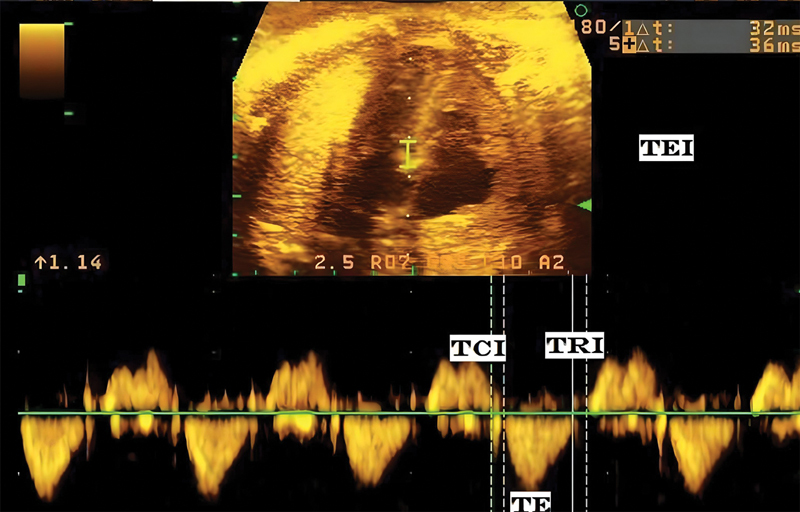

First, to explore differences in fetal cardiac function in patients with and without intrahepatic cholestasis of pregnancy (ICP) based on the TEI index. Second, to explore a potential correlation between TEI index and bile acid levels in pregnant women with ICP. Third, to study changes in the TEI index of fetuses from pregnant women with ICP after administration of ursodeoxycholic acid (UDCA).This is a prospective observational case-control study conducted at Hospital Clínico San José and Clínica RedSalud Vitacura, both in Santiago, Chile, between April 2018 and October 2020. ICP was defined as palmar-plantar pruritus of nocturnal predominance for more than 1 week associated with a total bile acid level above 10 μmol/L. Control cases were women with pregnancies scheduled for induction or elective cesarean section between 37 and 40 weeks of gestation according to current protocols. Differences in the TEI index between cases and controls were assessed by the Wilcoxon test. The correlation between the TEI index and bile acid levels was assessed by the Spearman correlation test. Changes in TEI index before and after administration of UDCA were analyzed by the paired samples Wilcoxon test.A total of 181 pregnant women were included in the study, 109 women with ICP and 72 controls. The median gestational age at inclusion was 35.9 weeks (interquartile range [IQR], 33.0-38.9). The median TEI index was 0.31 (IQR, 0.29-0.36); this was significantly longer in fetuses of women with ICP ([0.34, IQR, 0.30-0.38] vs. [0.30, IQR, 0.28-0.31], p < 0.001). There was a significant correlation between bile acid levels and TEI index (0.584, p < 0.001). In 21 fetuses, the TEI index was measured a second time, 2 weeks later, following UDCA administration. The median TEI index decreased significantly following UDCA administration (0.40 ms before treatment [IQR, 0.36-0.42] vs. 0.33 after treatment [IQR, 0.32-0.38], p = 0.001), p = 0.001).The TEI index is increased in fetuses of women with ICP. TEI index was significantly correlated with bile acid levels, and administration of UDCA significantly reduced the TEI index. · Significant correlation between TEI index and bile acid levels.. · Effect of UDCA treatment.. · clinical implications for monitoring and treatment..

Abstract Image